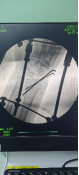

術中透視

患者男性,54歲,外傷致右側脛腓骨開放性骨折8小時,局部可見右側脛骨骨折近端露出···